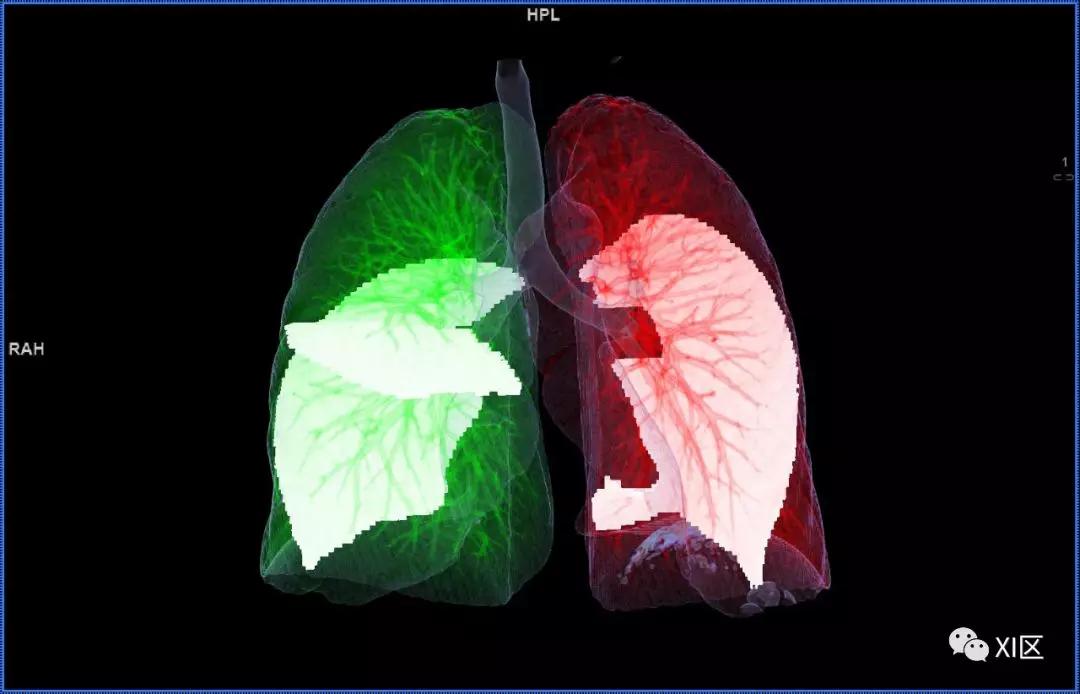

肺表面重建显示叶间裂和肺的分叶

透视图显示肺的叶间裂和肺的分叶